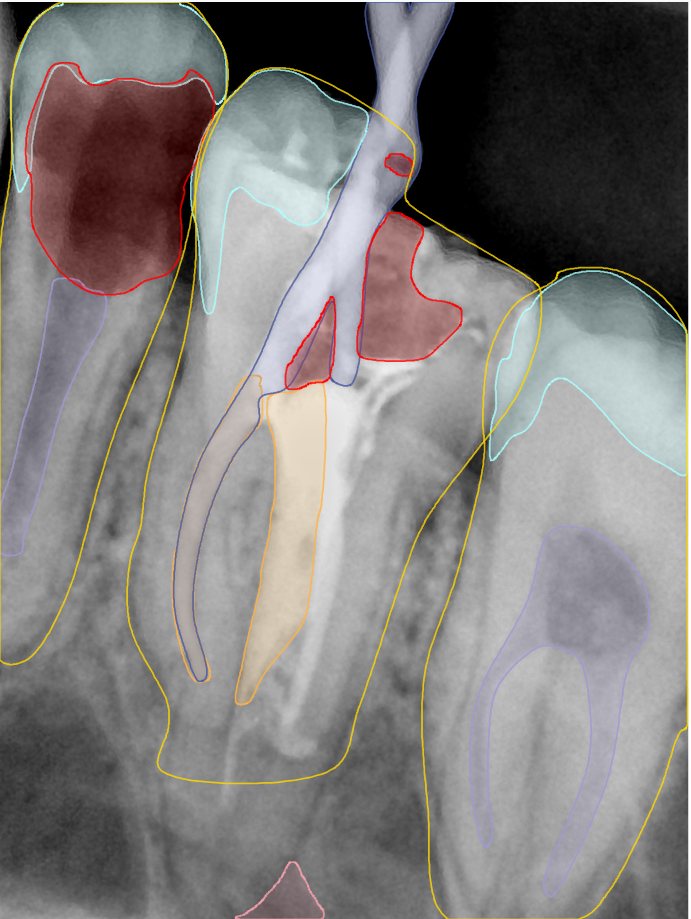

CR/DR 牙齿分割阶段记录

当前进展

- 完成了 CR/DR 牙齿相关分割训练

- 当前结果已经达到阶段预期,但仍有细节问题需要继续处理

相关测试

遇到的问题

- 训练过程中出现过 mask 下移问题

- 部分结果会出现 box 填充异常

- mask 边缘仍然有比较明显的锯齿感

参考

第二版算法问题测试

| 第一版 | 第二版 | 是否解决 | |

|---|---|---|---|

![]() | ![]() ![]() 边角识别有问题 龋齿识别不全 牙髓识别不全 | ![]() | 解决 |

![]() | ![]() 边角识别有问题 识别信息有误 自查(牙冠识别不全) | ![]() | 解决 |

![]() | ![]() ![]() 边角识别有误 大范围填充识别遗漏 | ![]() | 解决 |

![]() | ![]() 识别信息不全 | ![]() | 解决 |

![]() | ![]() ![]() 边角问题 牙胶识别不全 牙冠识别不全 | ![]() | 解决 |

![]() 换图片 | ![]() | ![]() 牙冠部分稍微白了一些就识别成小范围修补,部分判断异常 | 部分解决,修复类略敏感,牙冠部分稍微白了一些就识别成小范围修补,部分判断异常。 |

![]() | ![]() ![]() 牙冠识别不全 牙髓不全 根尖炎龋齿识别有误 | ![]() | 解决 |

![]() | ![]() | ![]() | 解决 |

![]() 换图片 | ![]() | ![]() | 解决 |

![]() | ![]() 牙冠识别有误 | ![]() | 解决 |

![]() 换图片 | ![]() ![]() 边角识别有误 | ![]() 修复类敏感 | 部分解决,图像过白,导致修复类判断异常。 |

![]() 换图片 | ![]() 牙冠识别不全 | ![]() 修复类敏感 | 部分解决,图像过白,导致修复类判断异常 |

结论:修复类出现了不鲁棒的情况,后续需要加入轮廓的扩充数据进行增强。